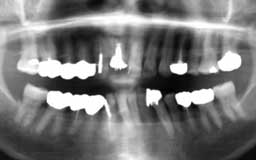

Kさん 初診時 49歳 女性

年齢の割に歯周疾患進行傾向が強く、上顎に残る1本も瀕死の状態です。このまま放置してお くと、下顎も2〜3年以内にほとんど全ての歯を失うことが予想されます

Kさん 17年後 66歳

下顎残存歯に対して、全ての神経を取ったのち歯周外科処置をと補綴物による連結固定を行 いメインテナンス継続